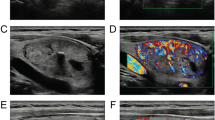

A physician more than 5-year experiences in ultrasound diagnosis marked the anteroposterior diameter and transverse diameter of the original standard images of 296 thyroid nodules with the cursor. Patient data and characteristics were blinded in AmCAD-UT application. Then the computer automatically traced the initial contour of ROI, identified the ultrasound image features of the thyroid nodules, then labeled and quantified the features in different colors, including echo type of the nodules, solid/cystic nature, uniformity of echo, nodular morphology, aspect ratio, and with or without microcalcification (Figs. 1, 2). Finally, the CAD system automatically generated the malignancy risk assessment report and suggestions of thyroid nodules based on 2015 ATA Guidelines [5], 2017 ACR TI-RADS Guidelines [8], 2016 AACE/ACE/AME Guidelines [18] and 2011 Kwak TI-RADS Guidelines [19] in the program.